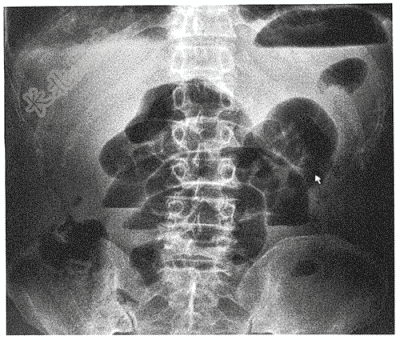

- 单项选择题患者男,46岁,因腹痛10小时急诊就诊。腹平片如图,请给出最可能的诊断( )

A、肠梗阻

B、急性胃肠穿孔

C、右输尿管结石

D、急性胃扩张

E、急性阑尾炎